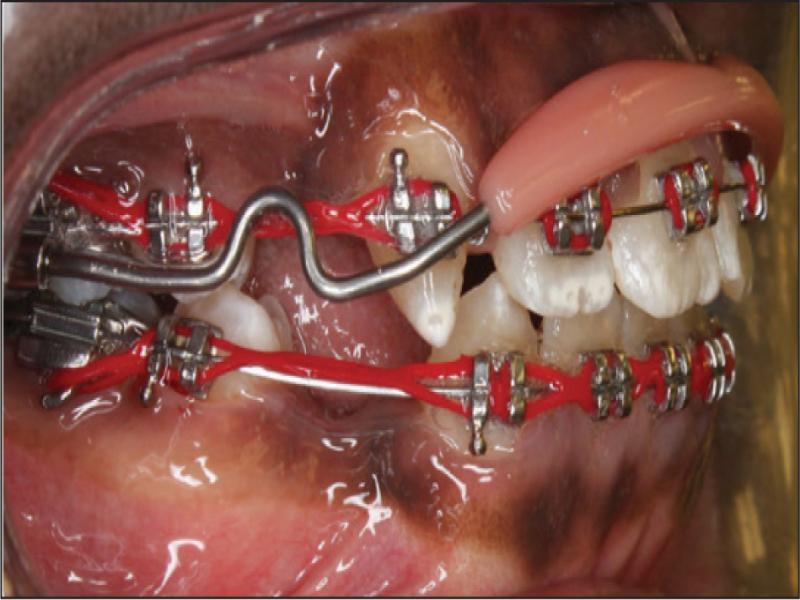

Treatment was initiated after the extraction of the recommended teeth. Banding and bonding were completed using 0.018″ × 0.025″ brackets of Roth prescription. Both arches were levelled and aligned using 0.014″ nitinol wire. The wires were upgraded to 0.016″ stainless steel wires, and power chains were used to retract the upper right canine and consolidate the lower canine-to-canine region to prepare for lower en masse retraction. After the lower anterior spaces were closed, a 0.016″ × 0.022″ nitinol wire with a reverse curve was inserted. The lower canine-to-canine region and the lower first molar to second premolar on both sides were consolidated using a stainless steel ligature wire, and a power chain was stretched from the lower second premolar to the lower canines. Due to its long root, a prefabricated upper lip bumper was inserted to reinforce upper arch anchorage during upper right canine retraction (Figure 4). Once the upper right canine was retracted, the upper lip bumper was removed, and an upper 0.016″ × 0.022″ stainless steel wire with keyhole loops was activated to retract the upper incisors. Palatal root torque was added to achieve bodily retraction of the upper incisors. After all space closure, upper and lower 0.016″ × 0.022″ nitinol wires were placed followed by 0.016″ × 0.022″ stainless steel wires for finishing and detailing using class II elastics as needed. To improve the aesthetics of the upper left first premolar, labial root torque was applied along with enameloplasty of the palatal cusp. Interproximal reduction of the upper incisors was performed to manage a Bolton discrepancy and improve overjet and overbite. Because fixed retainers were refused by the patient’s mother, modified upper and lower Hawley retainers were provided for retention. The patient was referred for aesthetic restoration of the upper right canine but chose not to proceed. The total treatment time was two years and eight months (Figures 5–8; Table I). Figure 9 shows images of the patient 19 months after active treatment. The result remained stable except for some extraction space opening distal to the lower canines.

A prefabricated upper lip bumper inserted to reinforce the upper anchorage during upper right canine retraction due to its long root.

Several factors require consideration when deciding to retain a deciduous canine and relate to the preference of the patient, the cost, and the type of underlying malocclusion. 20 In the present case, the patient had protruded and incompetent lips, proclined and protruded incisors and an anterior open bite, so an extraction treatment plan was chosen. Upper arch anchorage was needed because the upper right permanent canine had a long root and an upper lip bumper was inserted to provide posterior tooth support during permanent canine retraction. Alternative anchorage considerations were the use of miniscrews, a headgear, or a transpalatal arch. Although not usually used in the upper arch, 25-27 a lip bumper was placed since the upper bands were already prepared with headgear tubes and no patient compliance would be needed.